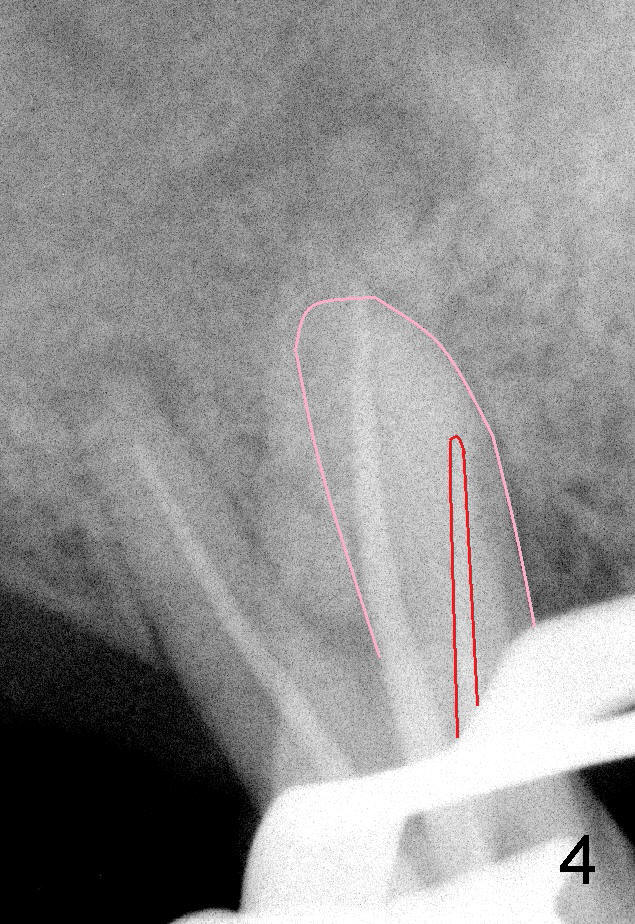

50岁男士有严重牙周炎(图一(2009年拍摄):二号牙(左上七)最终拔除(与图二对比)),最近三号牙(左上六)冷热痛,而且不能咬东西,三号牙多处牙周袋深,根尖片显示远中颊侧和腭侧根尖阴影(图二箭头),初步诊断:牙周牙髓综合症,需要根管治疗以及牙周手术,还可能保留不了。开髓表明活髓,近中颊侧和远中颊侧(DB)根管口很接近(参考图一图二),扩大(30/.04)后并表现不出来(图五至图七),开始近中根管口好像比较接近腭侧根管口,以为是MB2,使用Piezo超声波/diamond tip在MB(图六*)颊侧和近中寻找另外一个根管(箭头),但不成功。腭侧根管扩大到40/.06,匆匆忙忙插入主牙胶尖,拍摄根尖片(图三),显示远中颊侧以及腭侧(P)牙胶尖在相应牙根正中,但是近中颊侧并不是这样(图四=图三+MB牙根和牙胶尖轮廓),这说明还存在另外一个根管。经过再次合适扩大(crown down),腭侧牙胶尖进入更深地方(临床上),这时病人已经坐立不安了,paper points吸干根管后,拍摄图五至图七,暂封。由于病人还缺失好几颗牙齿,劝他去拍摄CT。今天术后第五六天,打电话给他,他很高兴,说冷热痛消失,牙齿也牢靠多了,但是还没去拍摄CT。下周三他回来完成根管治疗。

如果他还没有CT,我该怎么在没有外科显微镜下找遗留根管呢?MB和P根管口之间的确有一个沟(map),但是非常光滑(图五至图七),能找到根管口?还是往原来MB根管口颊侧探索?图三/图四暗示MB1还没有被发掘,对吗?MB2存在吗?